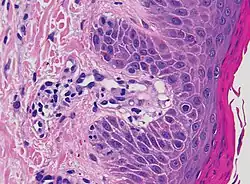

| Mycosis fungoides | Present | Focal | Regular or irregular | Normal | Normal | Minimal or no spongiosis; ±Pautrier microabscess | Atypical lymphoid cells lining the dermo–epidermal junction | ![]() |